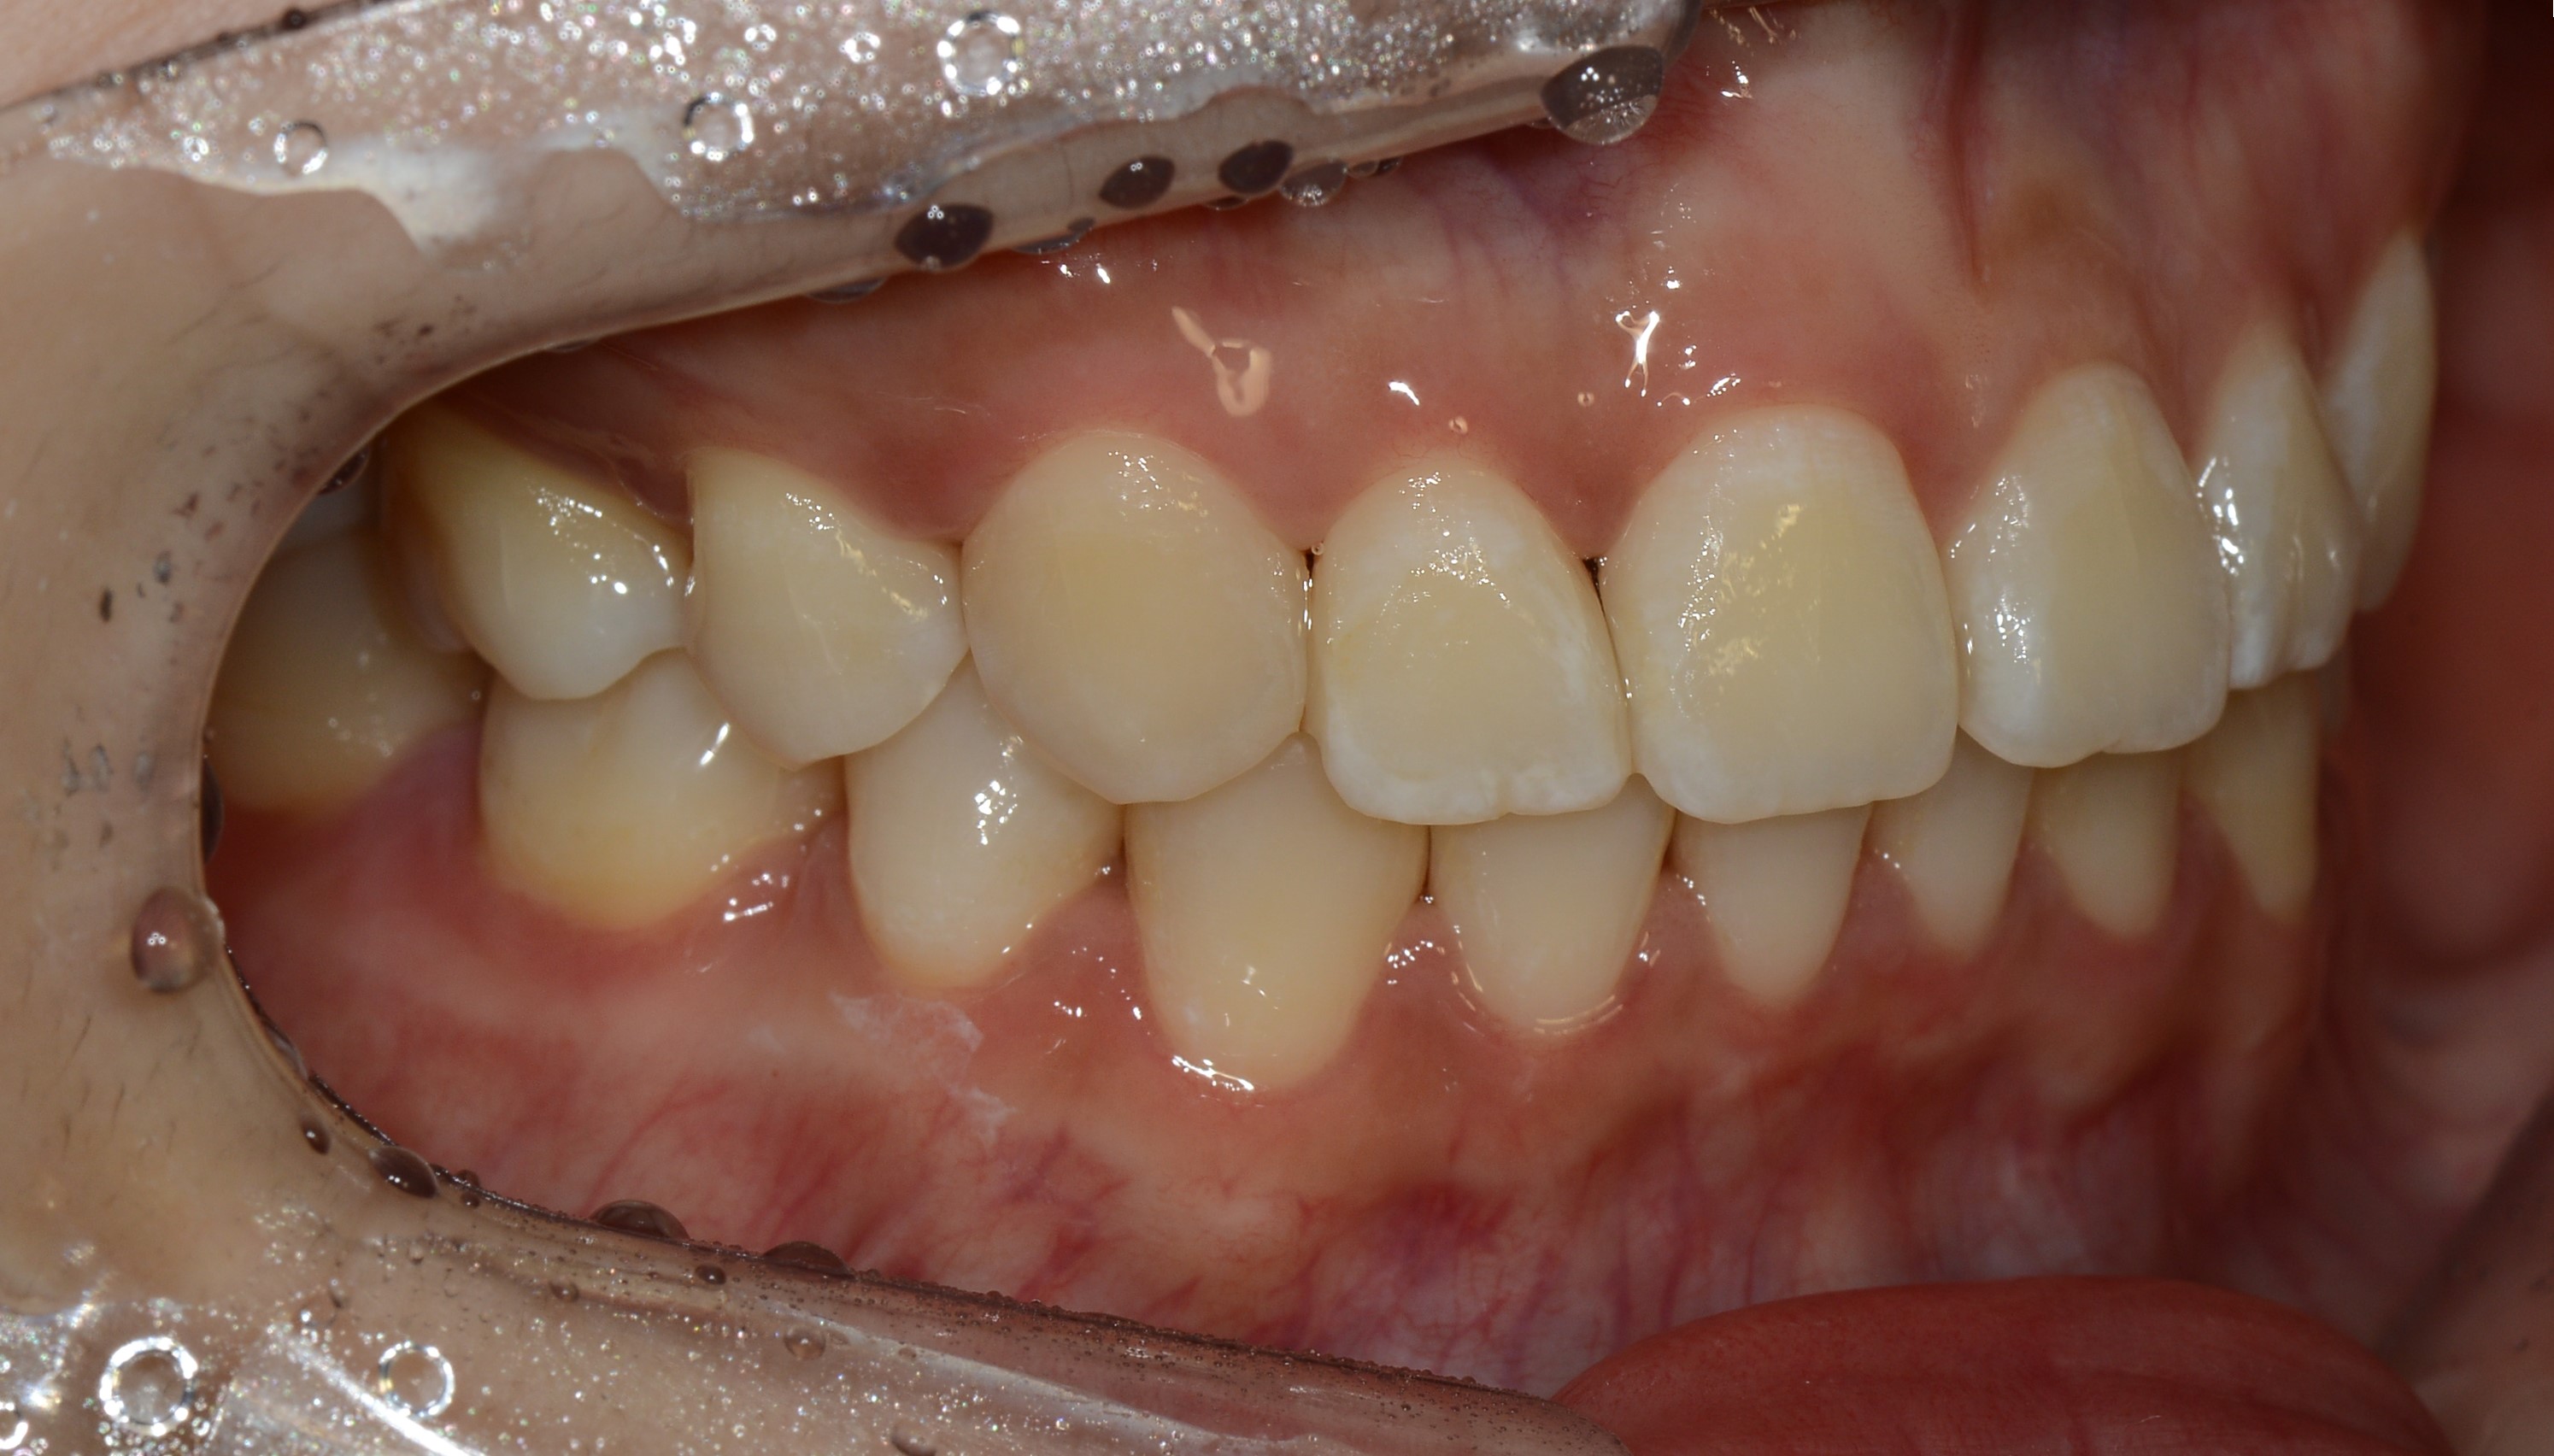

치료 후 사진입니다.